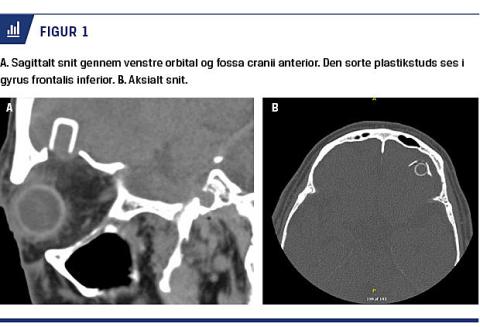

På hospitalet i Danmark blev der ved en CT afsløret et cylinderformet fremmedlegeme på 0,5 × 1 cm. Fremmedlegemet havde penetreret loftet af orbita og var endt intracerebralt ca. 1 cm inde i patientens venstre frontallap ved gyrus frontalis inferior (Figur 1).